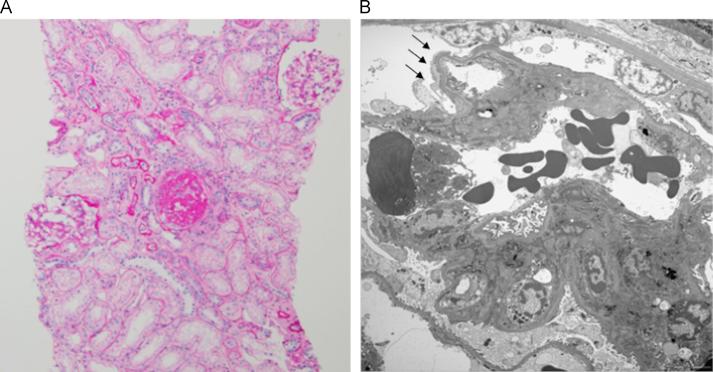

MYH9 nephropathy.

MYH9-related disorder is an autosomal dominant disease caused by a mutation in the MYH9 gene, which encodes nonmuscle myosin heavy chain IIA (NMMHC-IIA). This disease is characterized by giant platelets, thrombocytopenia, granulocyte inclusion bodies, proteinuria, and high-pitch sensorineural deafness. Nephropathy has been observed in 30% of patients with MYH9-related disorder. The characteristic features are early onset proteinuria and rapidly progressing renal disorder. However, the prognosis of MYH9 nephropathy remains unclear. Herein, we describe a 36-year-old woman who presented with proteinuria and was diagnosed with MYH9 nephropathy via renal biopsy and gene analysis. Her proteinuria improved after administration of an angiotensin II receptor blocker, but was aggravated after changing to a calcium channel blocker.

MYH9相关疾病是一种常染色体显性疾病,由MYH9基因突变引起,该基因编码非肌球蛋白重链IIA(NMMHC-IIA)。这种疾病的特征是巨大血小板、血小板减少、粒细胞包涵体、蛋白尿和高音调感音神经性耳聋。在30%的MYH9相关疾病患者中观察到肾病。其特征性表现为早期蛋白尿和快速进展的肾脏疾病。然而,MYH9肾病的预后仍不清楚。在此,我们描述了一名36岁的女性,她出现蛋白尿,经肾活检和基因分析被诊断为MYH9肾病。服用血管紧张素II受体阻滞剂后她的蛋白尿有所改善,但改用钙通道阻滞剂后病情加重。